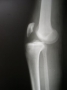

Paciente, sexo masculino, 20 anos, vítima de acidente motociclístico há 2 dias, evoluindo com dor e deformidade em joelho direito (Vide fotos).

Conduta realizada: Redução Incruenta + Fixação Transarticular (Vide fotos).